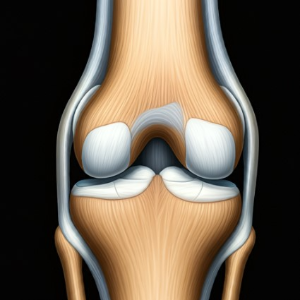

연골은 관절을 부드럽게 움직일 수 있도록 도와주는 쿠션 역할을 합니다. 그러나 나이가 들수록 연골은 자연스럽게 닳거나 손상되면서 관절의 마찰과 통증을 유발하게 됩니다. - 근육량 감소

특히 계단을 내려갈 때 무릎에 더 큰 부담이 가해져 통증이 심해질 수 있습니다. 이는 무릎 연골이 약해졌거나 손상되었음을 시사합니다. - 오랫동안 앉아 있다가 일어날 때 느껴지는 뻣뻣함

관절에서 '딸깍' 소리나 '삐걱' 소리가 자주 들리는 것은 관절 간 마찰이 증가했음을 나타낼 수 있습니다. 이는 연골의 손상이나 관절액 부족과 관련이 있습니다. - 가벼운 운동 후에도 오래 지속되는 통증